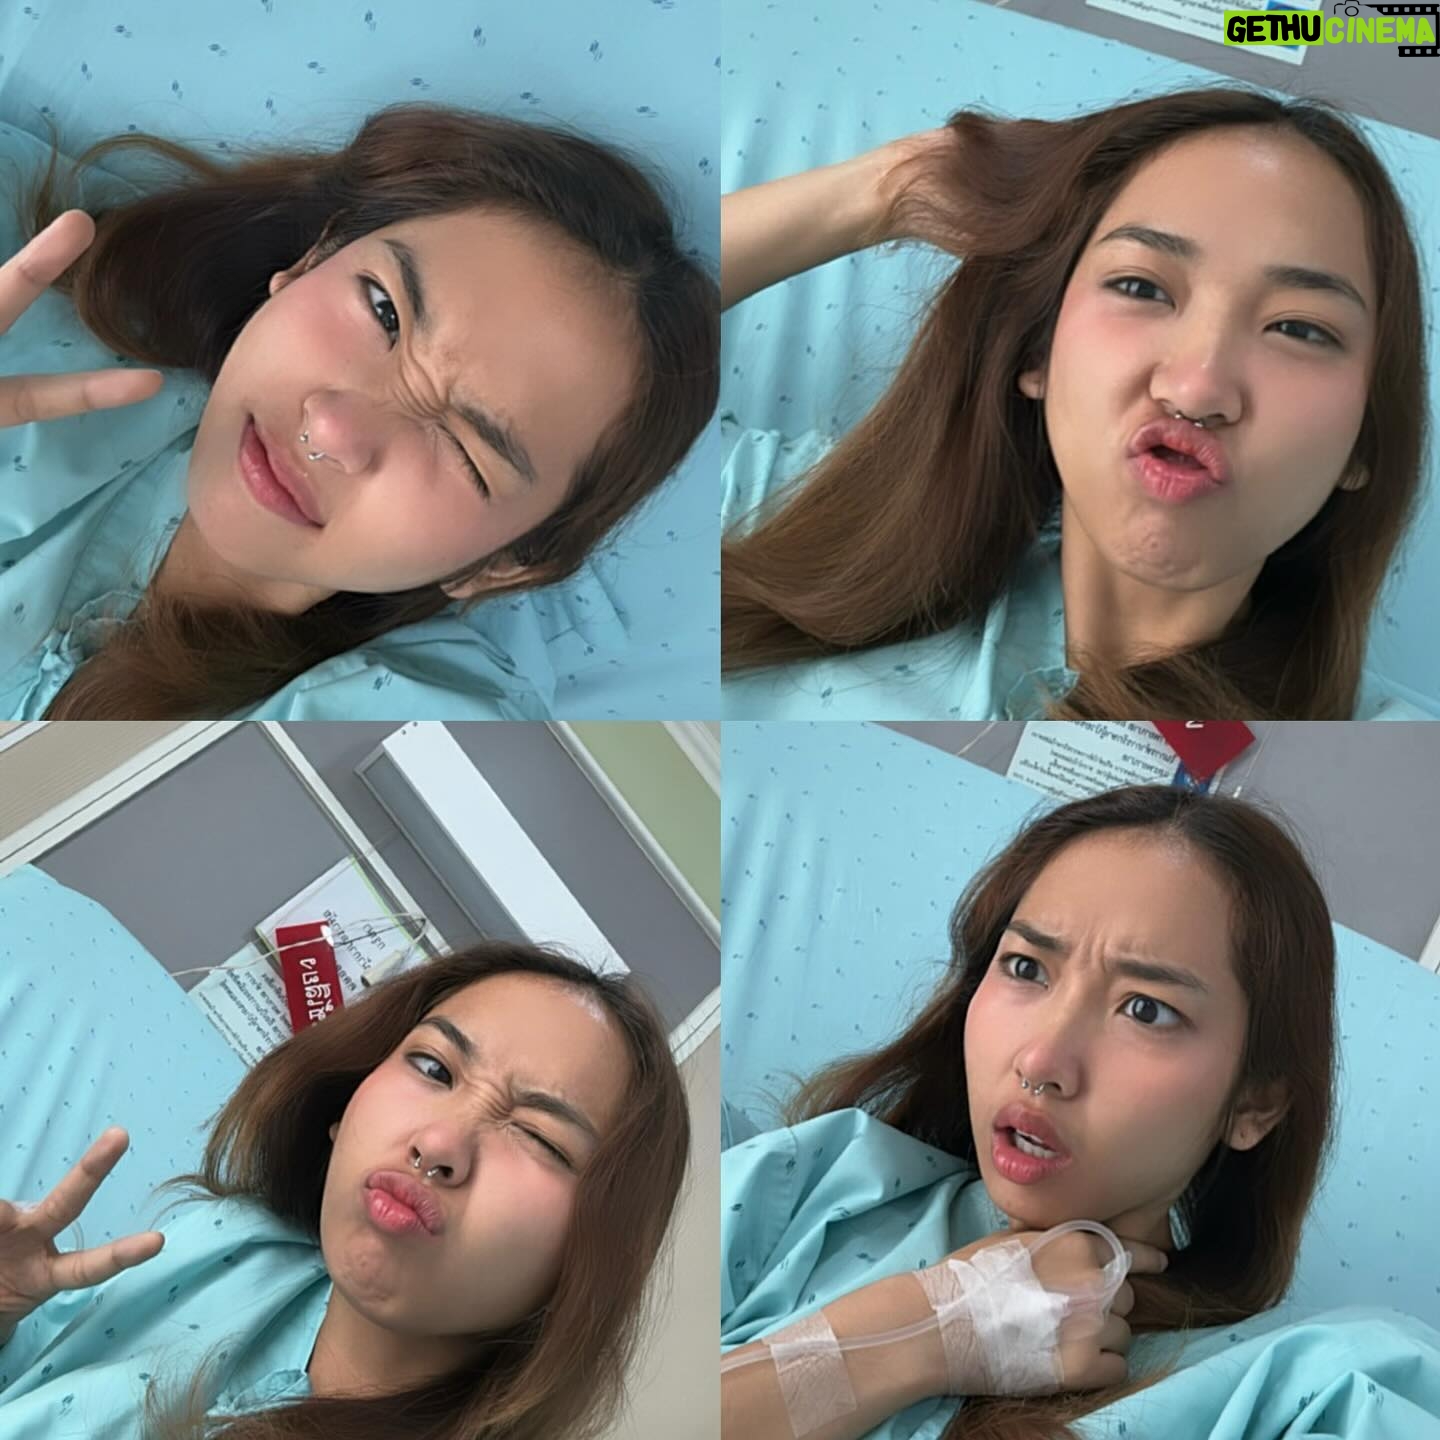

456.9K Likes – Danupha Khanatheerakul Instagram

Caption : สวัสดีค้าบ ส่งท้ายปีเก่าด้วยการ เป็นซีสต์ที่เส้นเสียง เย้ อ่าว ไม่ใช่ แฮะๆ หลังจากที่ใช้เสียงอยากต่อเนื่องไม่พักผ่อนนั้น มินก็เกิดอาหารคอแดงคอบวม (ซึ่งเป็นปกตินะฮะ เราพักผ่อนน้อยเองด้วย) เลยตัดสินใจไปตรวจที่โรงพยาบาลเฉพาะทาง และพบว่าตัวเป็น ซีสต์ที่เส้นเสียงข้างซ้ายข้างเดียว คือจะตัดออกก็ได้หรือจะปล่อยไว้ให้มันแตกเอง แต่มันก็อาจจะไม่แตกเองก็ได้ nobody knows คับ ถ้าผ่า โทนเสียงก็อาจจะเปลี่ยน แต่จริงๆคุณหมอบอกว่าไอ้ซีสต์นี้นวยก็น่าจะมีมาได้สักพักใหญ่ๆแล้วเนื่องจากโทนเสียงของนวยเปลี่ยนไปแล้วรอบนึง คือทุ้มต่ำลง ใช้เวลาตัดสินใจไป1สัปดาห์ ว่าจะผ่าตัดเอามันออก คือขึ้นชื่อว่าซีสต์ ตรงที่เส้นเสียงมันไม่ใช่ที่ที่มันควรอยู่อยู่แล้วอ่ะเนอะ ความจึ้งเกินอยู่ที่ว่า ก่อนหมอจะรมยาสลบ หนูสลบก่อนแล้ว กูหลับเบิ๊ดด หมอต้องปลุกมาดมยาสลบ55555 เลิศต่อมาคือ พอหมอสอดกล้องจะผ่าเอาอีก้อนออก ปรากฎว่า มัน already แตก แบบห๊ะ แบบร่างกายมัน heal ตัวเองไปแล้ว ซึ่งเป็นเรื่องดีนะคะ55555 เท่ากับว่าเราจะหายไวขึ้น ใช้เวลาพักฟื้นน้อยลง คุณหมอว่า โอกาสที่ซีสต์จะเองนี่ไม่ง่ายเลย แต่ก็ดีแล้วค่ะ หลังจากนั้นคือห้ามพูด สามวัน แต่ว่าอยากเล่าเรื่องราวให้พี่ๆฟังเลยส่งไปแบบคลิปสุดท้าย 5555555 สุดท้ายนี้ใครๆก็เป็นซีสต์ได้ รักษาเนื้อรักษาตัวไว้ด้วยนะคะทุกท่าน ปีนี้คงไม่ได้เจอกันในคอนแล้ว แต่อาจจะได้เจอมิลลิตามวัดหรือสถานที่สนุกๆนะคะ อิอิ เบิ้บบูทุกคนมากๆ ปีหน้าเจอกันใหม่ เสียงใสอย่างกับนกไนติงเกลค่ะ เสมอมาเสมอไป 🫶🏽✨Likes : 456898

456.9K Likes – Danupha Khanatheerakul Instagram

Caption : สวัสดีค้าบ ส่งท้ายปีเก่าด้วยการ เป็นซีสต์ที่เส้นเสียง เย้ อ่าว ไม่ใช่ แฮะๆ หลังจากที่ใช้เสียงอยากต่อเนื่องไม่พักผ่อนนั้น มินก็เกิดอาหารคอแดงคอบวม (ซึ่งเป็นปกตินะฮะ เราพักผ่อนน้อยเองด้วย) เลยตัดสินใจไปตรวจที่โรงพยาบาลเฉพาะทาง และพบว่าตัวเป็น ซีสต์ที่เส้นเสียงข้างซ้ายข้างเดียว คือจะตัดออกก็ได้หรือจะปล่อยไว้ให้มันแตกเอง แต่มันก็อาจจะไม่แตกเองก็ได้ nobody knows คับ ถ้าผ่า โทนเสียงก็อาจจะเปลี่ยน แต่จริงๆคุณหมอบอกว่าไอ้ซีสต์นี้นวยก็น่าจะมีมาได้สักพักใหญ่ๆแล้วเนื่องจากโทนเสียงของนวยเปลี่ยนไปแล้วรอบนึง คือทุ้มต่ำลง ใช้เวลาตัดสินใจไป1สัปดาห์ ว่าจะผ่าตัดเอามันออก คือขึ้นชื่อว่าซีสต์ ตรงที่เส้นเสียงมันไม่ใช่ที่ที่มันควรอยู่อยู่แล้วอ่ะเนอะ ความจึ้งเกินอยู่ที่ว่า ก่อนหมอจะรมยาสลบ หนูสลบก่อนแล้ว กูหลับเบิ๊ดด หมอต้องปลุกมาดมยาสลบ55555 เลิศต่อมาคือ พอหมอสอดกล้องจะผ่าเอาอีก้อนออก ปรากฎว่า มัน already แตก แบบห๊ะ แบบร่างกายมัน heal ตัวเองไปแล้ว ซึ่งเป็นเรื่องดีนะคะ55555 เท่ากับว่าเราจะหายไวขึ้น ใช้เวลาพักฟื้นน้อยลง คุณหมอว่า โอกาสที่ซีสต์จะเองนี่ไม่ง่ายเลย แต่ก็ดีแล้วค่ะ หลังจากนั้นคือห้ามพูด สามวัน แต่ว่าอยากเล่าเรื่องราวให้พี่ๆฟังเลยส่งไปแบบคลิปสุดท้าย 5555555 สุดท้ายนี้ใครๆก็เป็นซีสต์ได้ รักษาเนื้อรักษาตัวไว้ด้วยนะคะทุกท่าน ปีนี้คงไม่ได้เจอกันในคอนแล้ว แต่อาจจะได้เจอมิลลิตามวัดหรือสถานที่สนุกๆนะคะ อิอิ เบิ้บบูทุกคนมากๆ ปีหน้าเจอกันใหม่ เสียงใสอย่างกับนกไนติงเกลค่ะ เสมอมาเสมอไป 🫶🏽✨Likes : 456898

456.9K Likes – Danupha Khanatheerakul Instagram

Caption : สวัสดีค้าบ ส่งท้ายปีเก่าด้วยการ เป็นซีสต์ที่เส้นเสียง เย้ อ่าว ไม่ใช่ แฮะๆ หลังจากที่ใช้เสียงอยากต่อเนื่องไม่พักผ่อนนั้น มินก็เกิดอาหารคอแดงคอบวม (ซึ่งเป็นปกตินะฮะ เราพักผ่อนน้อยเองด้วย) เลยตัดสินใจไปตรวจที่โรงพยาบาลเฉพาะทาง และพบว่าตัวเป็น ซีสต์ที่เส้นเสียงข้างซ้ายข้างเดียว คือจะตัดออกก็ได้หรือจะปล่อยไว้ให้มันแตกเอง แต่มันก็อาจจะไม่แตกเองก็ได้ nobody knows คับ ถ้าผ่า โทนเสียงก็อาจจะเปลี่ยน แต่จริงๆคุณหมอบอกว่าไอ้ซีสต์นี้นวยก็น่าจะมีมาได้สักพักใหญ่ๆแล้วเนื่องจากโทนเสียงของนวยเปลี่ยนไปแล้วรอบนึง คือทุ้มต่ำลง ใช้เวลาตัดสินใจไป1สัปดาห์ ว่าจะผ่าตัดเอามันออก คือขึ้นชื่อว่าซีสต์ ตรงที่เส้นเสียงมันไม่ใช่ที่ที่มันควรอยู่อยู่แล้วอ่ะเนอะ ความจึ้งเกินอยู่ที่ว่า ก่อนหมอจะรมยาสลบ หนูสลบก่อนแล้ว กูหลับเบิ๊ดด หมอต้องปลุกมาดมยาสลบ55555 เลิศต่อมาคือ พอหมอสอดกล้องจะผ่าเอาอีก้อนออก ปรากฎว่า มัน already แตก แบบห๊ะ แบบร่างกายมัน heal ตัวเองไปแล้ว ซึ่งเป็นเรื่องดีนะคะ55555 เท่ากับว่าเราจะหายไวขึ้น ใช้เวลาพักฟื้นน้อยลง คุณหมอว่า โอกาสที่ซีสต์จะเองนี่ไม่ง่ายเลย แต่ก็ดีแล้วค่ะ หลังจากนั้นคือห้ามพูด สามวัน แต่ว่าอยากเล่าเรื่องราวให้พี่ๆฟังเลยส่งไปแบบคลิปสุดท้าย 5555555 สุดท้ายนี้ใครๆก็เป็นซีสต์ได้ รักษาเนื้อรักษาตัวไว้ด้วยนะคะทุกท่าน ปีนี้คงไม่ได้เจอกันในคอนแล้ว แต่อาจจะได้เจอมิลลิตามวัดหรือสถานที่สนุกๆนะคะ อิอิ เบิ้บบูทุกคนมากๆ ปีหน้าเจอกันใหม่ เสียงใสอย่างกับนกไนติงเกลค่ะ เสมอมาเสมอไป 🫶🏽✨Likes : 456898

456.9K Likes – Danupha Khanatheerakul Instagram

Caption : สวัสดีค้าบ ส่งท้ายปีเก่าด้วยการ เป็นซีสต์ที่เส้นเสียง เย้ อ่าว ไม่ใช่ แฮะๆ หลังจากที่ใช้เสียงอยากต่อเนื่องไม่พักผ่อนนั้น มินก็เกิดอาหารคอแดงคอบวม (ซึ่งเป็นปกตินะฮะ เราพักผ่อนน้อยเองด้วย) เลยตัดสินใจไปตรวจที่โรงพยาบาลเฉพาะทาง และพบว่าตัวเป็น ซีสต์ที่เส้นเสียงข้างซ้ายข้างเดียว คือจะตัดออกก็ได้หรือจะปล่อยไว้ให้มันแตกเอง แต่มันก็อาจจะไม่แตกเองก็ได้ nobody knows คับ ถ้าผ่า โทนเสียงก็อาจจะเปลี่ยน แต่จริงๆคุณหมอบอกว่าไอ้ซีสต์นี้นวยก็น่าจะมีมาได้สักพักใหญ่ๆแล้วเนื่องจากโทนเสียงของนวยเปลี่ยนไปแล้วรอบนึง คือทุ้มต่ำลง ใช้เวลาตัดสินใจไป1สัปดาห์ ว่าจะผ่าตัดเอามันออก คือขึ้นชื่อว่าซีสต์ ตรงที่เส้นเสียงมันไม่ใช่ที่ที่มันควรอยู่อยู่แล้วอ่ะเนอะ ความจึ้งเกินอยู่ที่ว่า ก่อนหมอจะรมยาสลบ หนูสลบก่อนแล้ว กูหลับเบิ๊ดด หมอต้องปลุกมาดมยาสลบ55555 เลิศต่อมาคือ พอหมอสอดกล้องจะผ่าเอาอีก้อนออก ปรากฎว่า มัน already แตก แบบห๊ะ แบบร่างกายมัน heal ตัวเองไปแล้ว ซึ่งเป็นเรื่องดีนะคะ55555 เท่ากับว่าเราจะหายไวขึ้น ใช้เวลาพักฟื้นน้อยลง คุณหมอว่า โอกาสที่ซีสต์จะเองนี่ไม่ง่ายเลย แต่ก็ดีแล้วค่ะ หลังจากนั้นคือห้ามพูด สามวัน แต่ว่าอยากเล่าเรื่องราวให้พี่ๆฟังเลยส่งไปแบบคลิปสุดท้าย 5555555 สุดท้ายนี้ใครๆก็เป็นซีสต์ได้ รักษาเนื้อรักษาตัวไว้ด้วยนะคะทุกท่าน ปีนี้คงไม่ได้เจอกันในคอนแล้ว แต่อาจจะได้เจอมิลลิตามวัดหรือสถานที่สนุกๆนะคะ อิอิ เบิ้บบูทุกคนมากๆ ปีหน้าเจอกันใหม่ เสียงใสอย่างกับนกไนติงเกลค่ะ เสมอมาเสมอไป 🫶🏽✨Likes : 456898